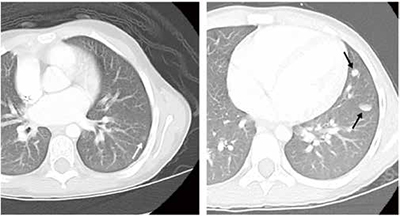

2个周期的长春新碱、放线菌素D、多柔比星(DD-4A方案)化疗后,研究者采用胸部CT评估肺结节应答情况,以确定肺结节快速完全缓解(RCR)队列和肺结节缓慢的不完全缓解(SIR)队列;在两个队列中比较肺转移数量和大小对无事件生存(EFS)和总生存(OS)的影响,其中RCR队列接受额外的DD-4A方案但不接受肺部放疗,SIR队列接受原来的三药加环磷酰胺/依托泊苷(M方案)并配合肺部放疗。

结果显示,AREN0533试验共招募288例仅伴肺转移的Ⅳ期患儿,其中251例符合纳入标准并接受分析。在RCR队列(105例)中,肺转移数量对EFS和OS无显著影响;肺转移大小显著影响EFS(P=0.022),但对OS无显著影响。在SIR队列(146例)中,肺转移数量或大小对EFS和OS均无显著影响。